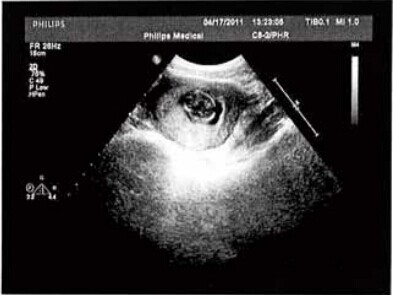

妈妈肚子里的小宝宝让人最感兴趣的问题就是宝宝是男是女啊,众所周知除非有什么特殊原因,一般情况下医院是不允许用B超来检验宝宝性别,当然孕妇询问也是拒绝回答的,如果你现在马上要去做b超了,,然而医生知道你怀的是男宝宝还是女宝宝,可她又不告诉你,那怎么办?别着急,再怎么样B超单总要给吧!

偷偷地告诉你:B超单有一个妙处,就是我们可以从B超单看出生的是男宝宝还是女宝宝啦:

其一: 看数据,假如长度和宽度的相差在一倍以上说明是男宝宝哦。长和宽相等女宝宝可能性大。

其二: 看形状,像茄子或长条状的是男宝宝可能性大,圆圆的是女宝宝可能性大。